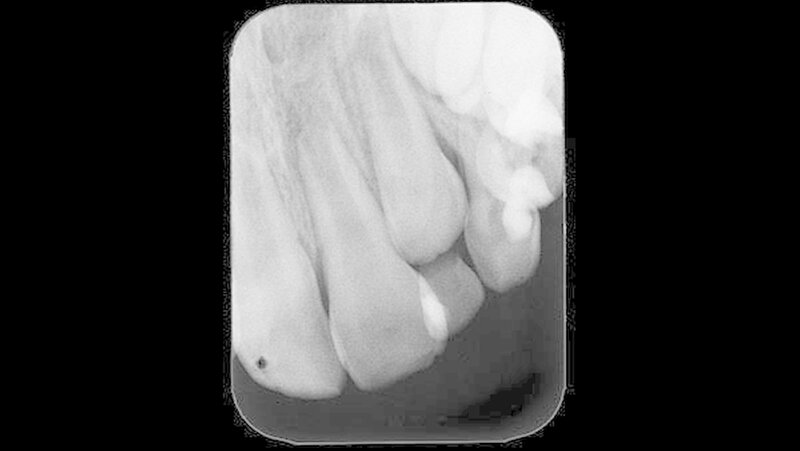

Auch zehn Monate nach Behandlungsübernahme, in denen in einem Abstand von vier bis sechs Wochen Kalziumhydroxideinlagen in den gereinigten Wurzelkanal eingebracht wurden, war der Patient zwar beschwerdefrei, der Wurzelkanal jedoch nicht zu trocknen. Aus diesem Grund wurde eine weitere Zahnfilmaufnahme zur weitergehenden Diagnostik angefertigt (Abbildung 3).

Der Zahnfilm ließ im Vergleich zur Voraufnahme bei Behandlungsübernahme eine Reduktion der apikalen Osteolyse und eine Abnahme der Radiotranslumniszenz erkennen. Dies wurde als fortschreitender Heilungsprozess bei ossärer Regeneration bewertet. Über weitere zwölf Monate erfolgte somit in einem vier- bis sechswöchigen Turnus eine schonende Reinigung und Desinfektion nach dem geschilderten Vorgehen und eine wiederholte Kalziumhydroxideinlage mit abschließendem bakteriendichten Verschluss.